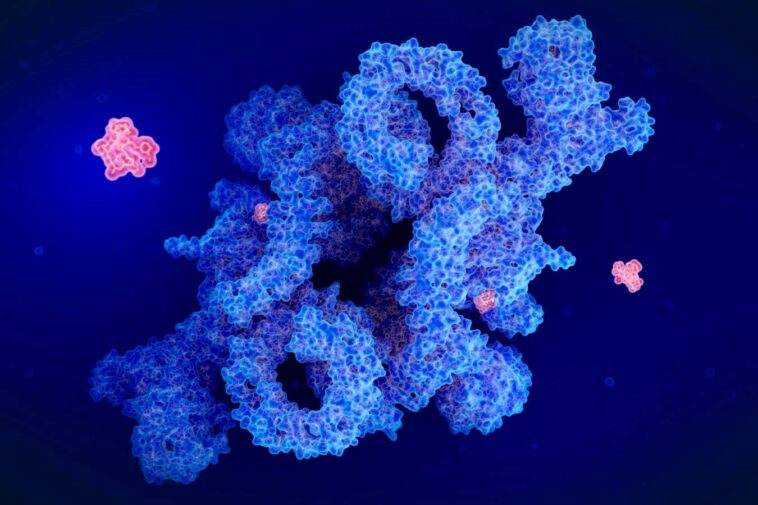

Une illustration du médicament rapamycine (rouge) inhibant le complexe protéique MTORC1, qui a divers effets sur la fonction cellulaire